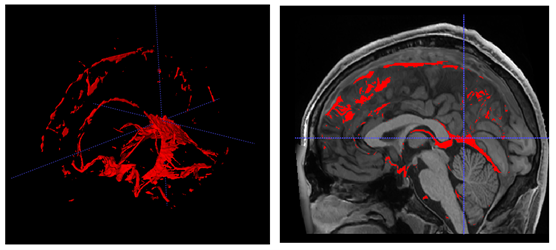

Vessels and connective tissue

After the whole integration process, we automatically performed a 3D hole filling operation over the binary mask formed by the sum of all the defined structures (i.e. the foreground) to get a solid intracranial cavity volume (no holes). We named the label corresponding to the filled regions as “vessels+ connective tissue” as this label is mainly related to these tissues. Figure 10 shows an example of this label. This label allows to have a more compact brain anatomy and to fully define all the structures with the intracranial volume (ICV).

Refer to caption

Figure 10: Right: Example of Vessels and connective tissue. Left: 3D representation of this label.